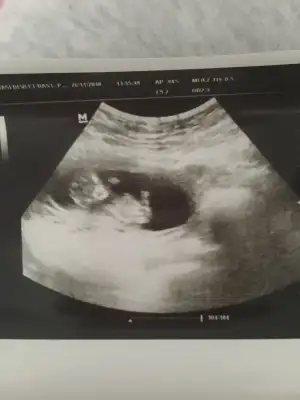

Kızlar pazartesi doktora gitmiştim ama paylaşmaya bir türlü firsatım olmadı. Sat’a göre 1 hafta önden gidiyor bizimki. Doktor cinsiyeti gördü ama söylemiyeceğim dedi emin olamadım dedi ve söylemedi. Sizce ney Cinsiyet tahmini alayım :KK54:

Birde miniğim çok fena hareketliydi ilk etapda uyuyordu sanırım, doktor uyandırdı cihazla bi kaç kez hafif hafif vurdu karnıma miniğimde tepkisiz kalmadı.

Eklentiler

• DA4E9486-E0F7-4DE7-93FE-78ECA5BDF81B.webp